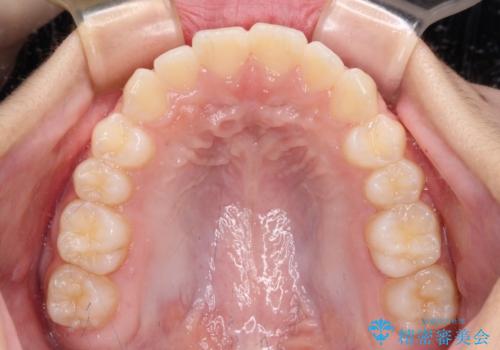

- 前歯のデコボコを気にして来院された高校生の患者様です。

捻れた前歯が前方に飛び出している点も気になっており、目立たない装置を希望されたため、インビザラインを用いて矯正治療を行うこととしました。

上下ともに少し捻れが残っていたため、治療の継続を提案しましたが、本人も親御さんも満足とのことで、治療を終えました。

捻れの改善により突出感も改善されました。